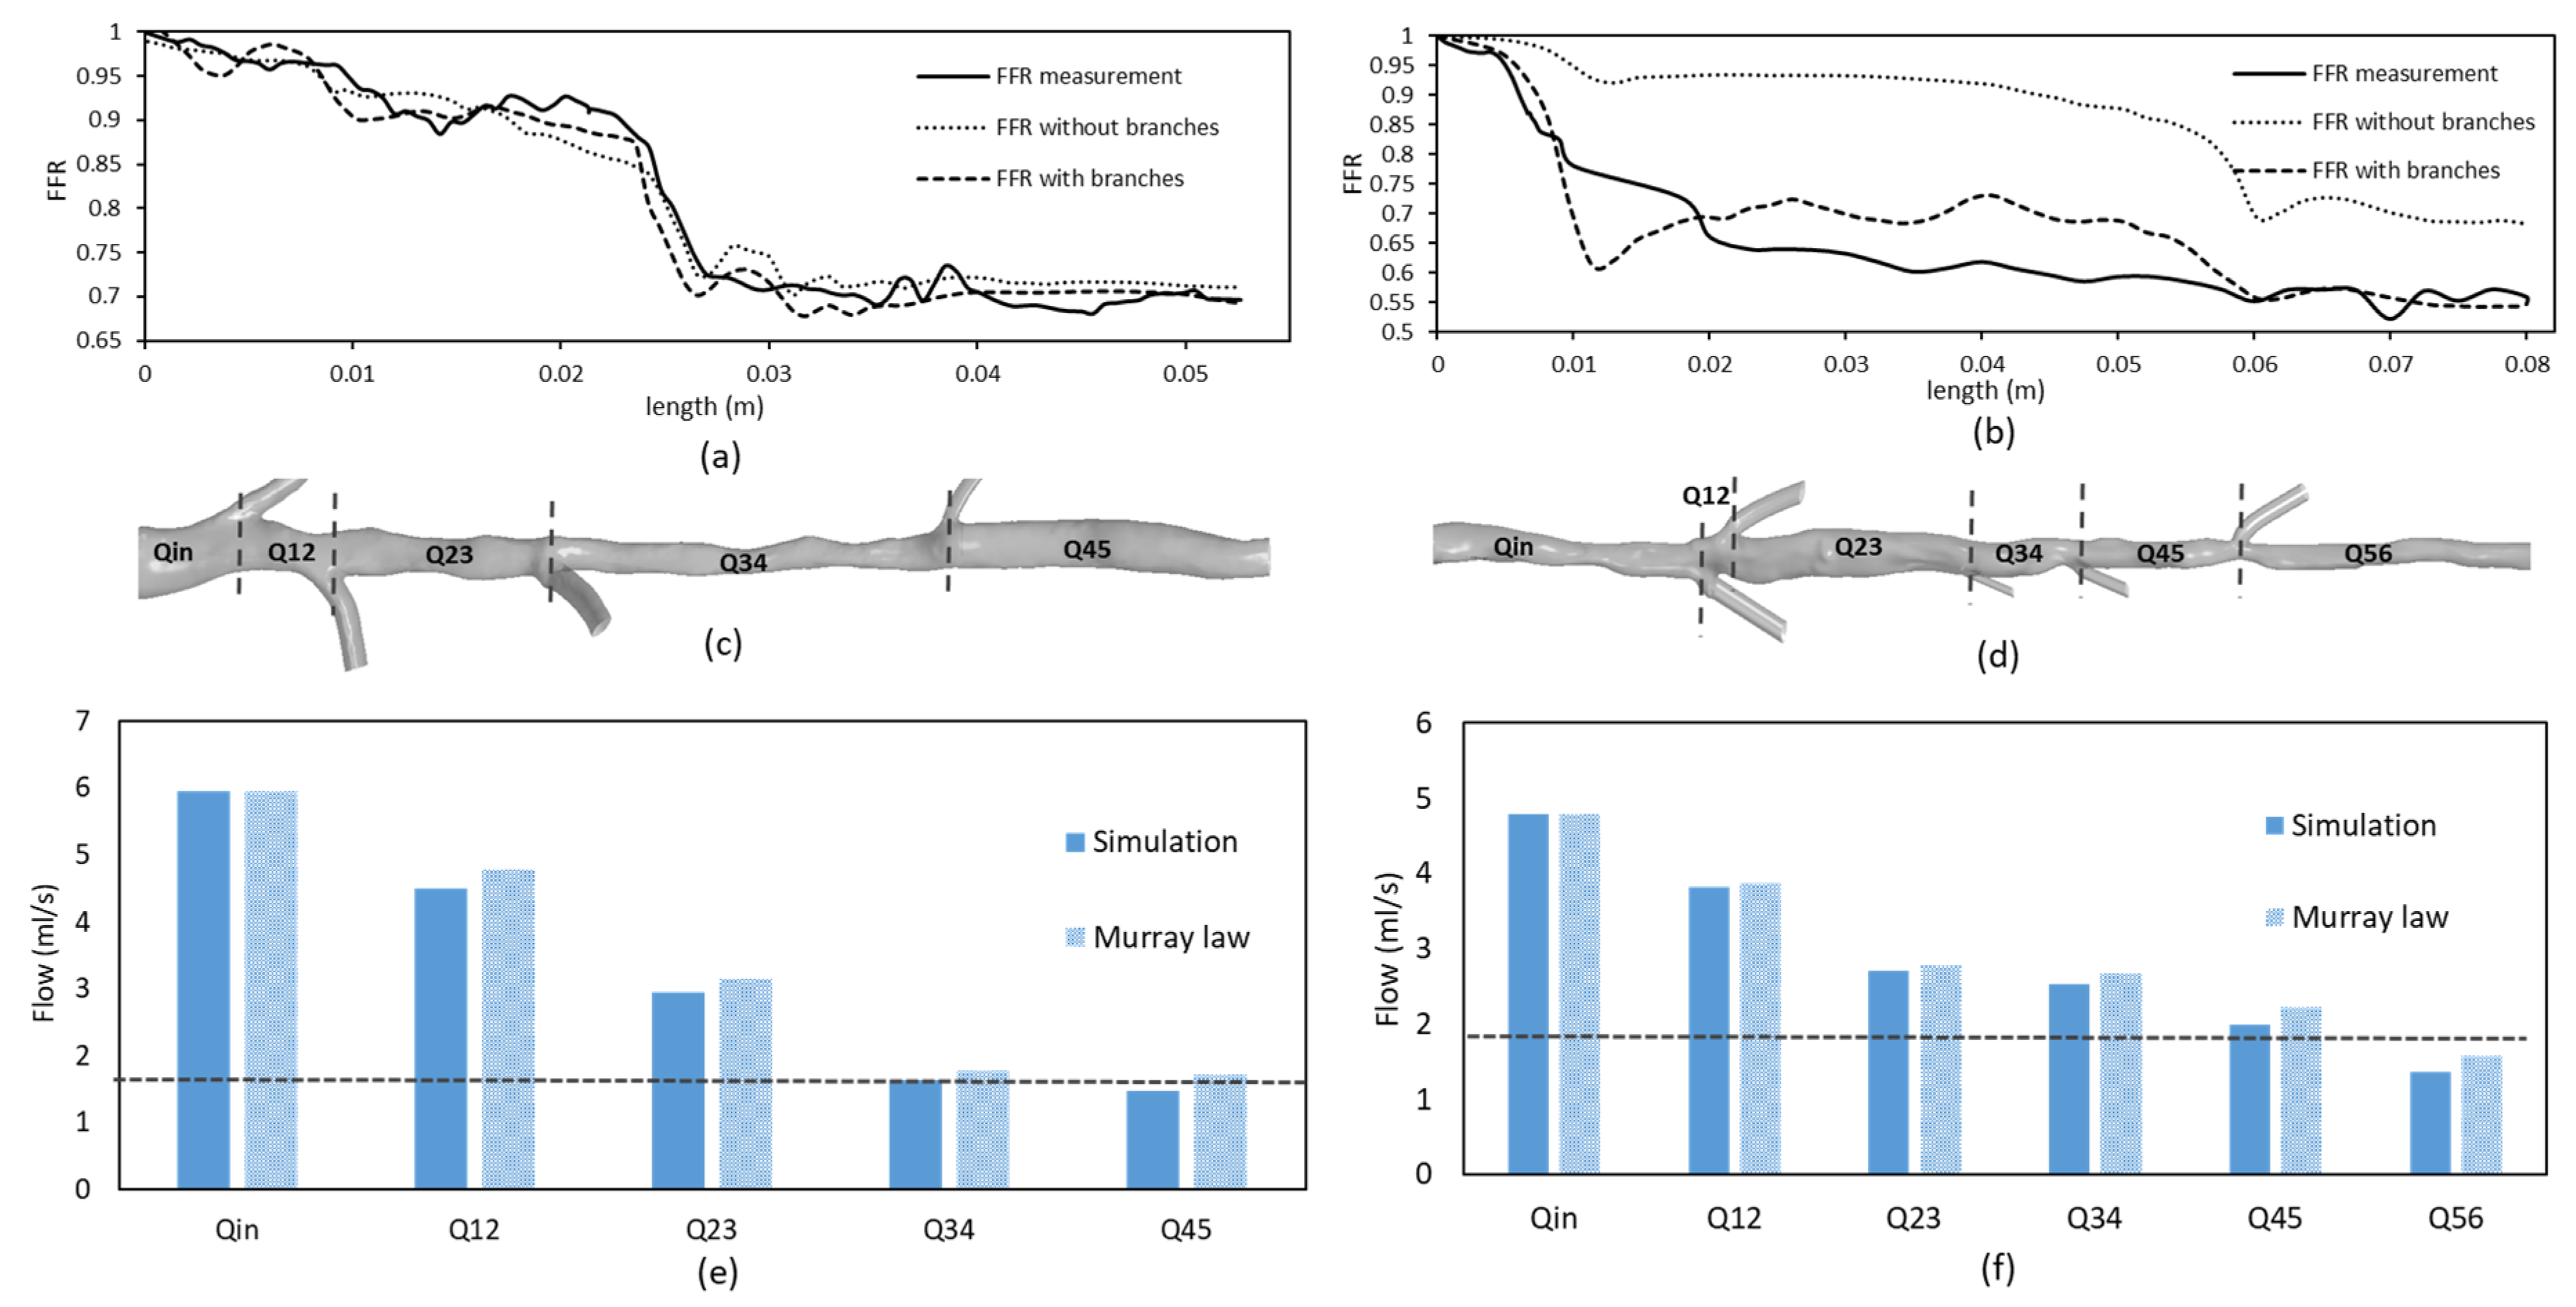

3.2. FFR Analysis in OCT-Reconstructed Vessel Models

3.3. Implications on FFR Computation Using OCT Imaging